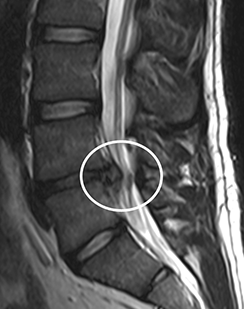

허리 디스크 (요추 추간판 탈출증)

요추 추간판(허리 디스크)의 수핵이 빠져나와 신경뿌리나 척수를 누르게

되어 통증을 유발하고,심한 경우에는 다리에 힘이 빠질 수 있습니다.